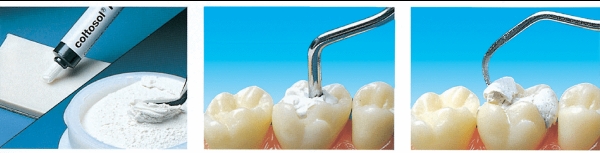

Sử dụng chất trám răng tạm thời để làm gì? Các vật liệu trám răng tạm thời đóng vai trò quan trọng trong việc bảo vệ răng bị tổn thương trước khi tiến hành điều trị lâu dài. Mỗi loại vật liệu đều có đặc tính riêng, giúp đảm bảo chức năng và sự thoải mái cho bệnh nhân trong thời gian chờ đợi. Dưới đây là một số loại chất trám răng tạm thời phổ biến:

- Cavit: Đây là một loại vật liệu trám răng tạm thời phổ biến, thường được sử dụng trong quá trình điều trị viêm tủy hoặc để bảo vệ răng trong thời gian ngắn. Cavit dễ dàng sử dụng và có khả năng bám dính tốt, giúp bảo vệ răng khỏi vi khuẩn và mảng bám.

Thời gian miếng trám răng tạm thời có thể giữ được phụ thuộc vào loại vật liệu được sử dụng và tình trạng răng của bạn. Tuy nhiên, thông thường miếng trám răng tạm thời có thể giữ được từ vài tuần đến vài tháng.

Bạn có thể tham khảo thêm ý kiến của nha sĩ để hiểu rõ hơn về những thông tin về loại chất trám răng tạm thời mà bạn sẽ sử dụng. Đồng thời, hãy tuân thủ hướng dẫn của nha sĩ và quay lại thăm khám đúng thời gian để đảm bảo răng được chăm sóc và điều trị tốt nhất.